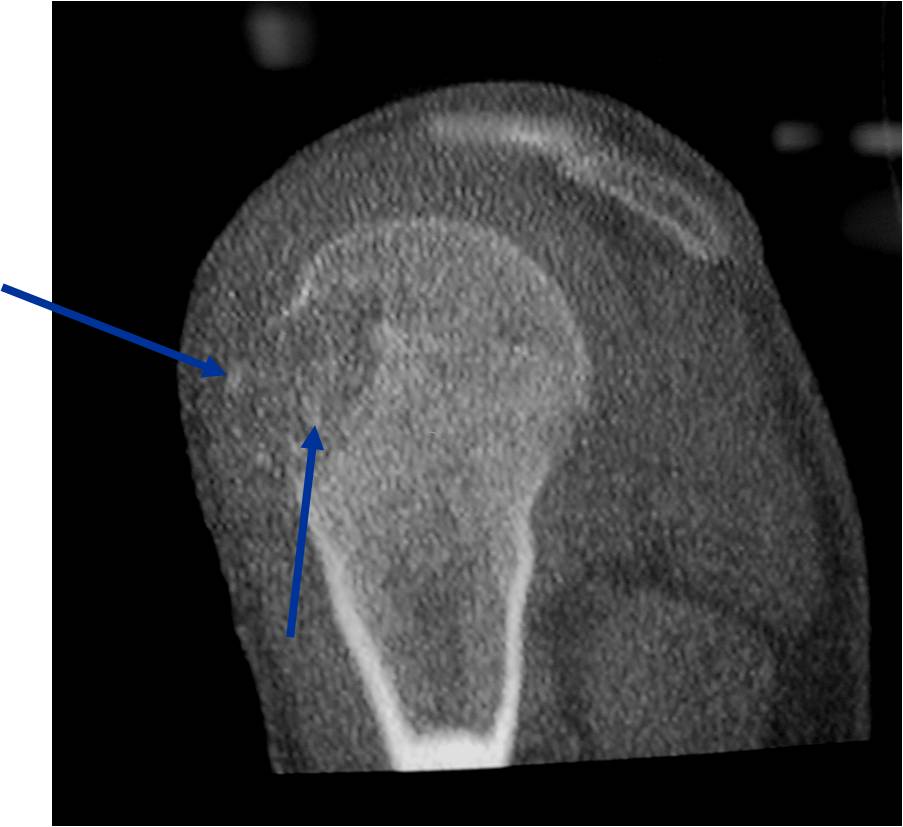

General Information Enchondroma is a benign indolent intramedullary hyaline cartilage neoplasm Accounts for 10% of all benign osseous tumors Limited growth, most lesions are less than 5 cm in maximal dimension Bones grow from a cartilaginous growth plate that...